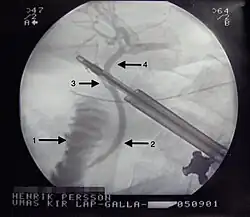

Injury of the bile ducts can be prevented and treated by routinely using X-ray investigation of the bile ducts (intraoperative cholangiography (IOC)).[24] This method was assessed by the Swedish SBU and routine use deemed to decrease risk of injury and morbidity following unaddressed injury while only increasing cancer rates due to radiation exposure by a lesser fraction.[24]

Peroperative Endoscopic Retrograde Cholangio-Pancreaticography (ERCP)/ Laparo-endoscopic rendezvous (LERV) technique

CBDS are found in 10–15% of patients during cholecystectomy when intraoperative cholangiography (IOC) is routinely performed.[31] [32] There are several strategies to manage choledocholithiasis but the optimal method as well as the timing of treatment is still under debate.[33]

In recent years the LERV technique, in which access to the common bile duct by ERCP is facilitated by an antegrade guidewire, which is intraoperatively introduced during fluoroscopy and is advanced through the cystic duct to the duodenum, has been established as an alternative to treat common bile duct stones discovered during laparoscopic cholecystectomy. This technique was first described in 1993 by Deslandres et al.[34] and has, in several studies, been shown to have a high rate of CBD stones clearance and a reduced number of complications, particularly post-ERCP pancreatitis, in comparison with conventional ERCP.[35] [36] This is probably due to the facilitated access to the common bile duct with a lesser degree of manipulation and trauma to the papilla Vateri. In a study by Swahn et al. the rendezvous method was shown to reduce the risk of PEP from 3.6 to 2.2% compared with conventional biliary cannulation.[37] The success rate of passing the transcystic guidewire into the duodenum has been reported to be over 80%.[38]